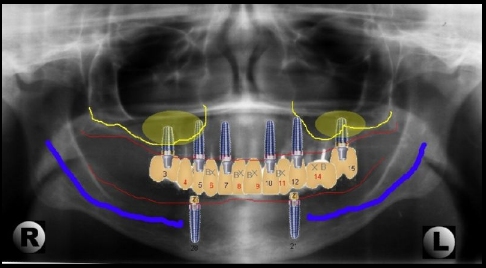

Conebeam.com a comprehensive website devoted to the art and science of conebeam ct scanners has an excellent review of all the different implant planning and surgical guide products. An astonishing 10 different systems are available. Most of the usual vendors: Materialise, Nobel Biocare Teeth in an hour, Denx and ILS are listed, but also some new and innovative systems from smaller vendors.

RoboDent`s navigation and implant placement planning software works with its Lapdoc system to give realtime visual feedback on the angle, depth and direction of implant placement. It uses 5mm titanium microspheres attached to the handpiece to track the position of the drill tip in realtime allowing the implantologist to see the depth and angle of implant placement.

DenX`s innovative CT-image driven implant planning and placement system, `IGI`, was recently honoured with a Medical Design Excellence Award. IGI allows a virtual implant to be placed on the CT image with the assistance of advanced planning tools. During the surgical procedure, the clinician guides the implant to the precise location, angle and depth required according to the plan. Real-time localization feedback assisted by audio and visual media allows the clinician to monitor the success of the procedure and avoid